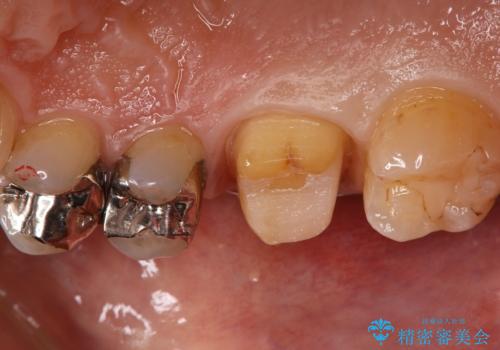

- 銀歯のセラミックへのやり替えをご希望で来院されました。

銀歯が入ってる歯は複数箇所ありましたが、咬合力がより強く破折リスクが高い奥歯から治療を開始してます。

奥歯の噛み合わせが強く、治療後にセラミックが割れるリスクがあった為マウスピースの装着をして頂いてます。